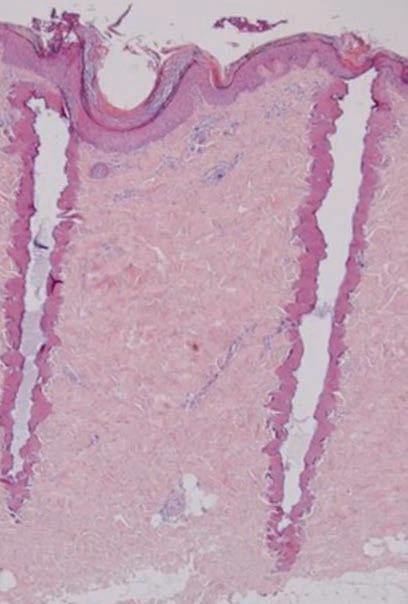

CO2 laser

for scar improvement: so what’s new? Drs Helen Douglas, Suzanne Rea & Anna Goodwin-Walters